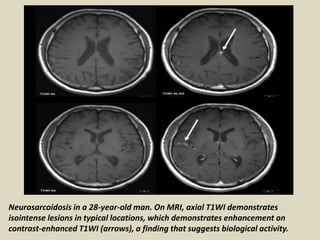

Neurosarcoidosis in a 28-year-old man. On MRI, axial T1WI demonstrates

isointense lesions in typical locations, which demonstrates enhancement on

contrast-enhanced T1WI (arrows), a finding that suggests biological activity.